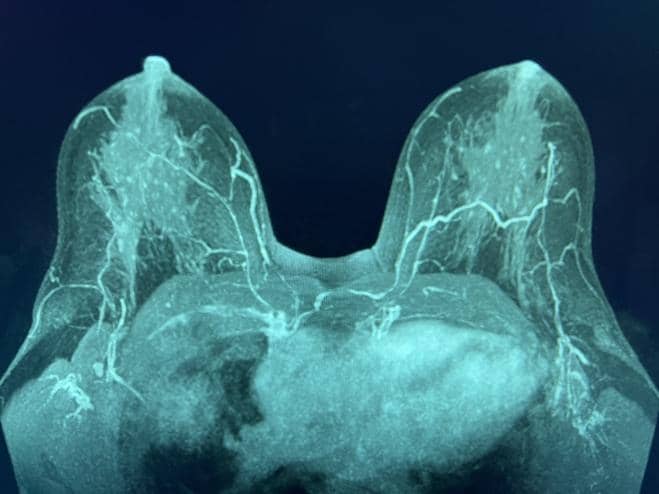

Şekil 1. MRG MIP, NAC'ye seyahat eden, meme başından üstün (solda) ve meme başı seviyesinde (sağda) IMP'leri gösterir.

Birden fazla dilimin ortalamasını alan yaygın bir yeniden format olan meme MRG MIP (maksimal yoğunluk projeksiyonu) görüntüleri, NAC'ye baskın kan akışını açıkça görselleştirdi (Şekil 1). Bilateral dominant IMP'ler, 2. ve/veya 3. interkostal boşluklarda (ICS) sternal sınır boyunca pektoralis majör kasından yayılır. Daha sonra, damarlar memenin deri altı dokusunda öne doğru seyretti ve NAC'nin yakınında sonlandı.

Önemli NAC kan kaynağını korumak için IMP-NSM cerrahi tekniği, önemli adımları içeren daha önce yayınlanmıştır. 1, 11, 12 Kontrastlı meme MRG, preoperatif evreleme için elde edilirse, en iyi MIP görüntülerinde görselleştirilen NAC kan akışını açıkça gösterebilir. Bu, tipik olarak IMP'den iki taraflı olarak, genellikle sternal sınır boyunca 2. veya 3. ICS'den kaynaklanan baskın NAC kan kaynağını gösterir (Şekil 1).

2.-4. ICS, sternal sınırın 1 cm lateralinde cilt üzerinde işaretlenir, bu da ana IMP damarlarının tanımlandığı ve pektoralis majör kasının önünde korunduğu ortak alanları gösterir. IMP-NSM tekniği, meme MRG'si olmadan, bu olağan yerleri işaretleyerek ve daha sonra bu alanlarda dikkatli bir diseksiyon yaparak gerçekleştirilebilir; bununla birlikte, varsa, meme MRG görüntüleri IMP kan temini hakkında yararlı bilgiler sağlayabilir ve ameliyattaki yeri tahmin edebilir. IMP-NSM, NAC'ye baskın IMP kan akışını korumak olarak tanımlanır; bununla birlikte, teknik, ilişkili ACN duyusal dallarına ek olarak, sternal sınır boyunca görselleştirilen ve vasküler beslemeye katkıda bulunabilecek ek küçük baskın olmayan IMP damarlarının korunmasını içerecek şekilde gelişmiştir. (Şekil 1 ve 2).